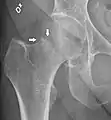

X-ray showing a suspected compressive subcapital fracture as a radiodense line

CT scan shows the same, atypical for a fracture since the cortex is coherent

T1-weighted, turbo spin echo, MRI confirms a fracture, as the surrounding bone marrow has low signal from edema.